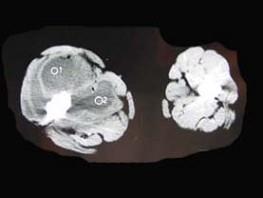

问题 男,15岁,一星期前寒战,继而体温急剧升高,达3940℃,发病后12天患肢右大腿出现功能障碍。局部出现红、肿、热、痛等症状,触之有波动感。实验室检查,血中白细胞升高,血沉增快,血培养阳性,中性粒细胞轻度升高,请结合所提供的图像,选择最佳选项 ( )

选项 A、动脉瘤样骨囊肿 B、骨巨细胞瘤 C、慢性化脓性骨髓炎 D、软骨肉瘤 E、急性化脓性骨髓炎

答案 E